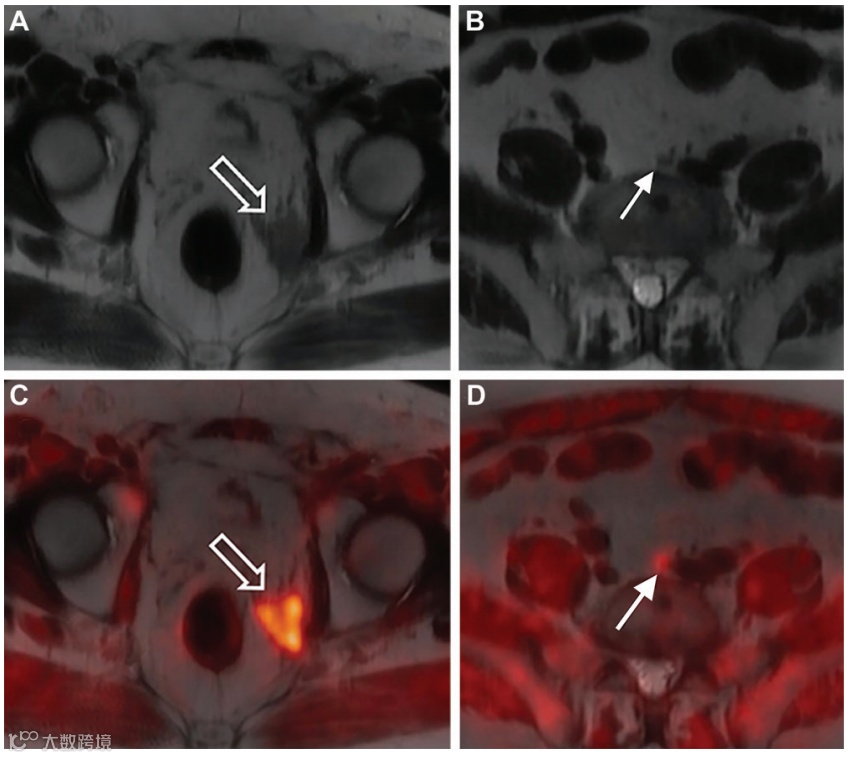

图4. 一名69岁男性的Fluciclovine PET/MRI。该患者5年前因Gleason 4+3级前列腺癌行前列腺切除术,近期血清前列腺特异性抗原(PSA)水平升高(最新值为2.1纳克/毫升)。进行Fluciclovine PET/MRI检查以评估生化复发情况并制定治疗方案。

(A、B) 轴向T2加权MR图像显示左侧前列腺切除床存在不对称的T2低信号(A中箭头所示),左侧髂总淋巴结(B中箭头所示)直径小于1厘米。

(C、D)在融合的PET/MR图像上,两个病灶(箭头所示)均显示Fluciclovine活性,与前列腺癌相符。